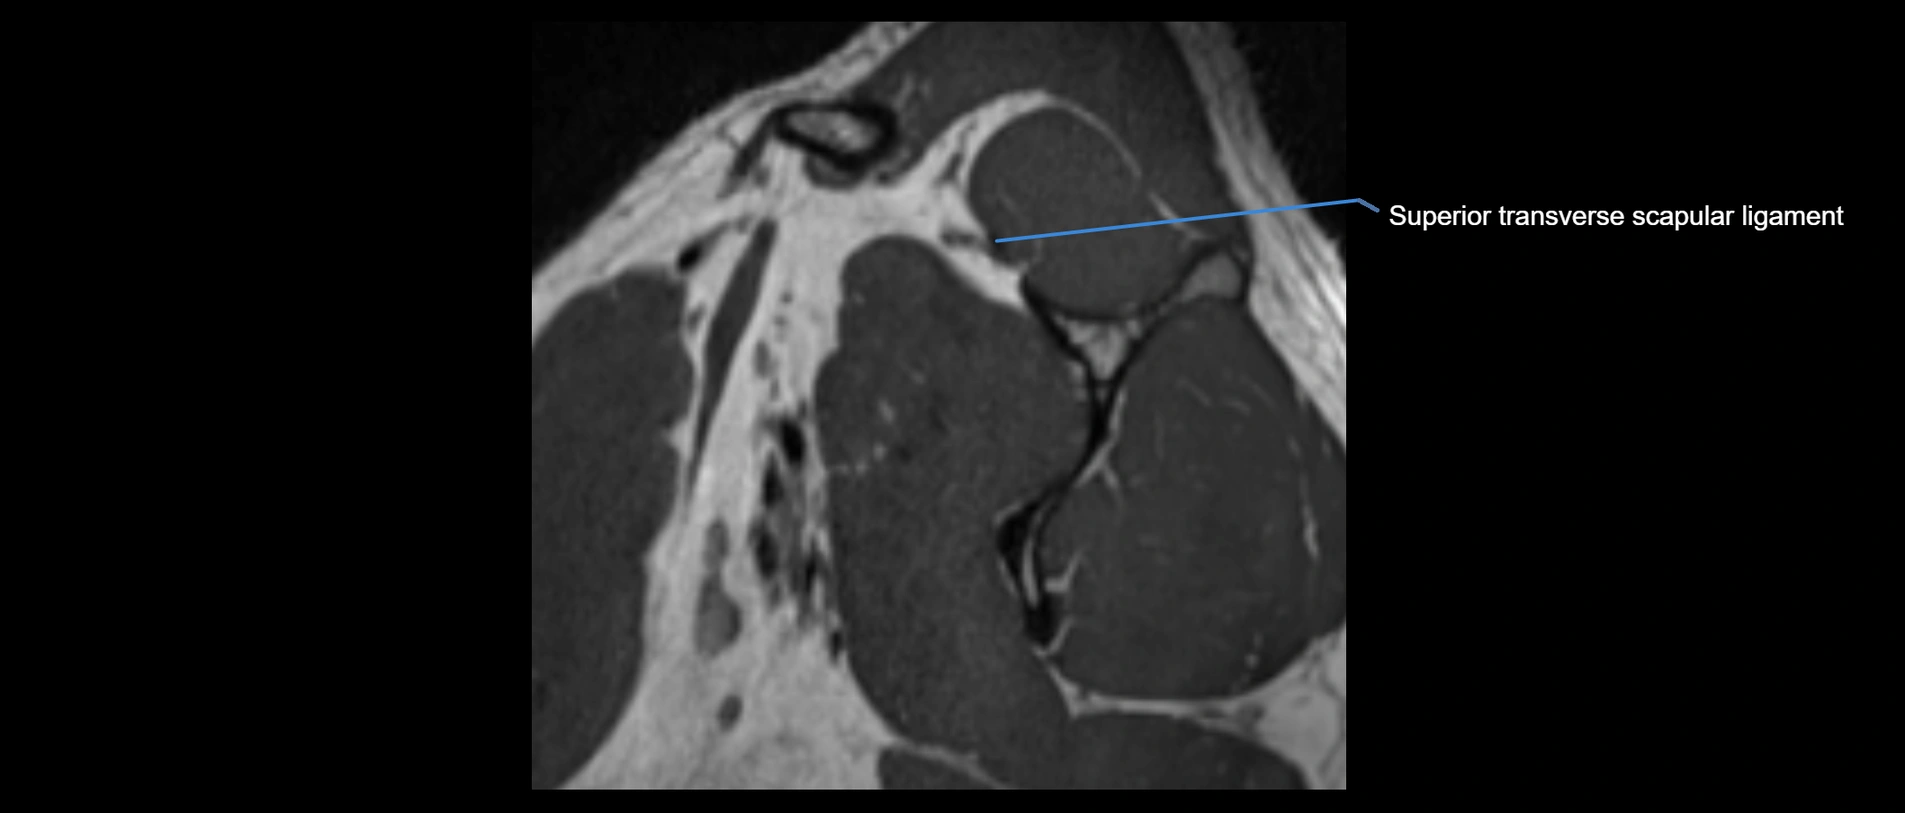

MRI images

image